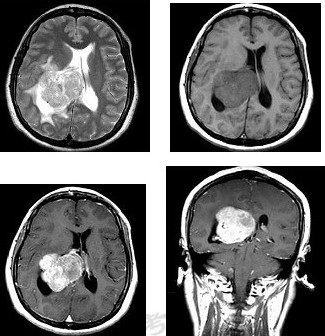

女,45岁,右眼视力下降8个月,右颜面麻木半个月,时有头昏,味觉减退,请根据所提供图像,选择最可能的诊断

A:(右侧脑室)脑膜瘤(合体细胞型)

B:(右侧脑室)室管膜瘤

C:(右侧脑室)脉络膜乳头状瘤

D:(右侧脑室)胶质瘤

E:(右侧脑室)转移瘤